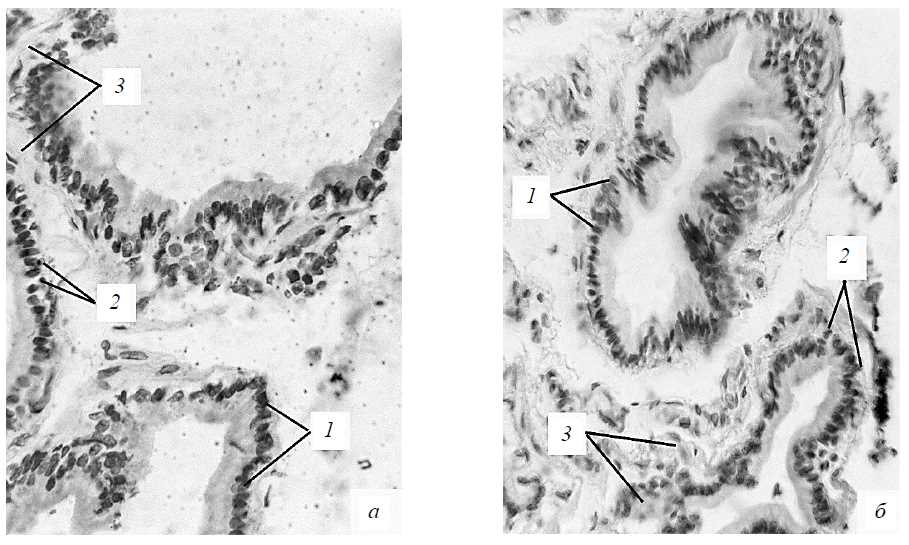

Секреторная часть предстательной железы крыс репродуктивного периода имеет разветвленную альвеолярно-трубчатую структуру. Строму органа представляет фиброзно-мышечный каркас. Концевые отделы органа имеют округлую или вытянутую форму, часто образуют складки, их просвет содержит ацидофильный секрет. Концевые отделы железы выстланы однослойным призматическим эпителием, включающим секреторные и базальные клетки. Ядра эпителиоцитов имеют преимущественно овальную форму и располагаются эксцентрично (рис. 1).

Рис. 1. Участок предстательной железы животных репродуктивного возраста на 15-е сутки наблюдения: а – после применения циклофосфамида; б – в контроле; 1 – эпителий желез; 2 – соединительная ткань. Окраска гематоксилин-эозином. Увеличение: приближение – zoom 18,5; объектив – PlanCN 10x/0,25 ∞/-/FN22

Рис. 3. Участок предстательной железы неполовозрелых крыс на 15-е сутки наблюдения: а – после применения циклофосфамида; б – в контроле; 1 – ядра секреторных эпителиоцитов; 2 – базальные клетки; 3 – соединительная ткань. Окраска гематоксилин-эозином. Увеличение: приближение – zoom 18,5; объектив – Plan CN40x/0.65 ∞/0.17/FN22